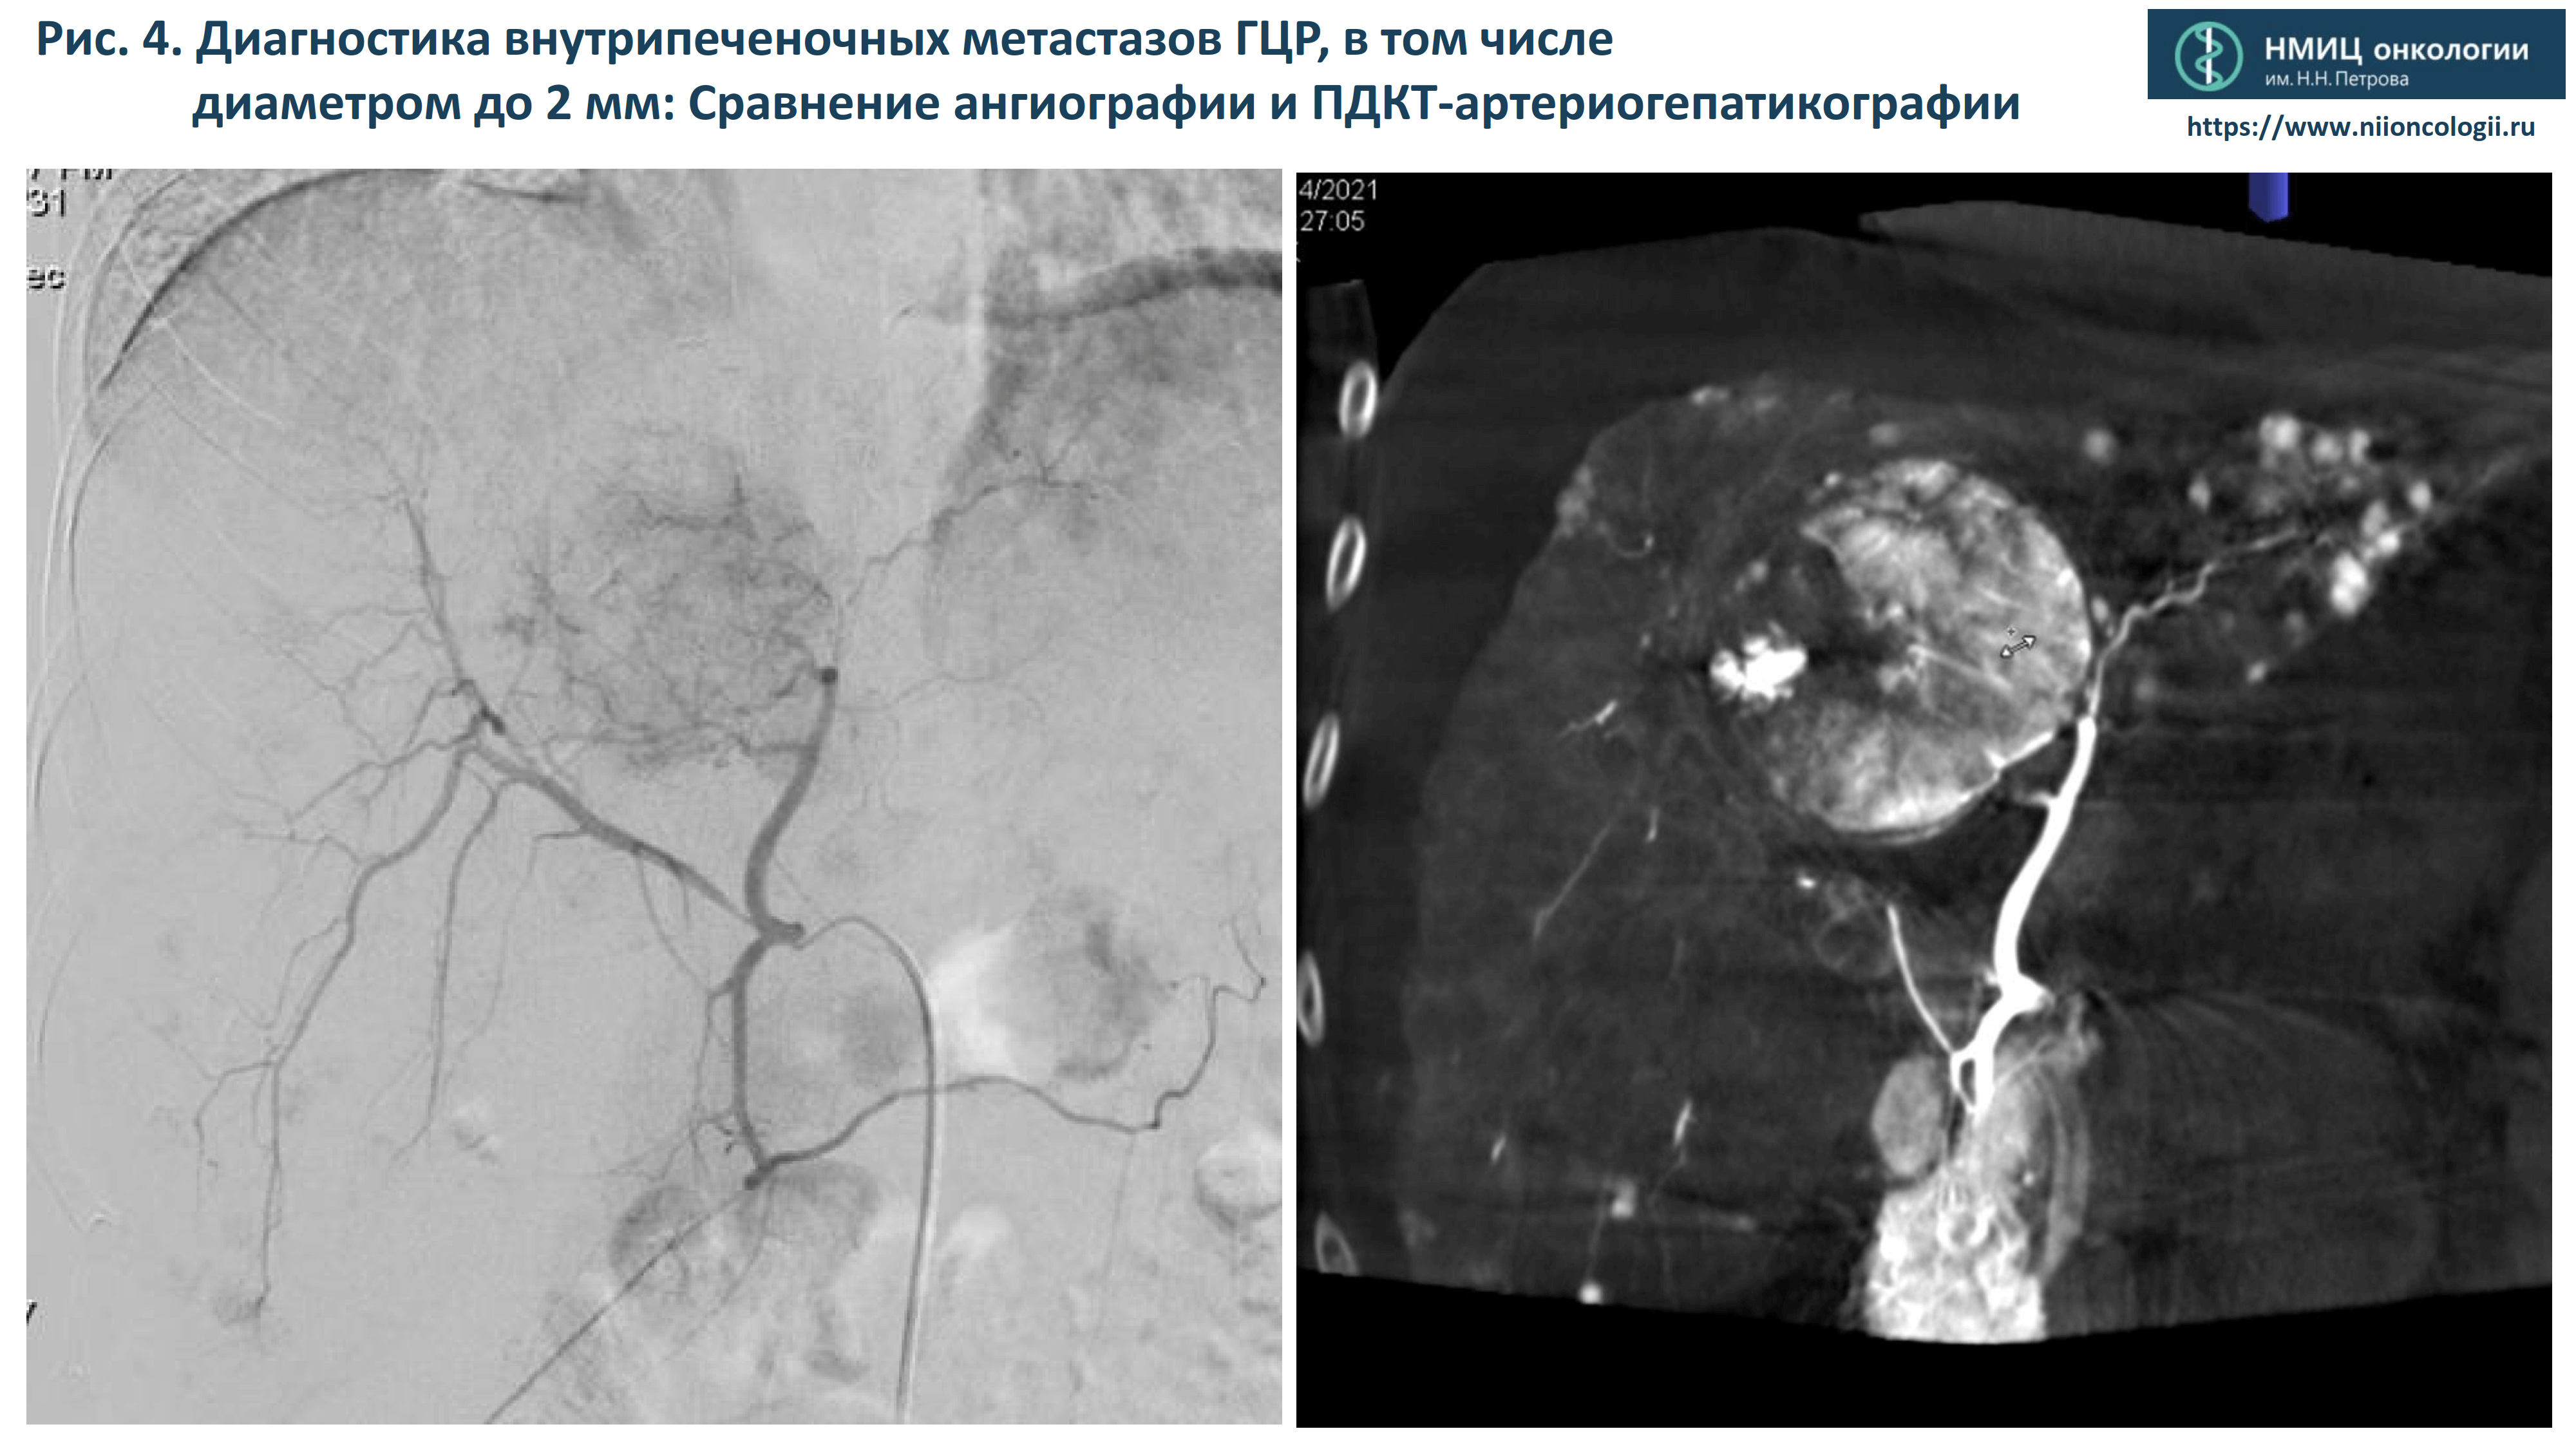

- Диагностика внутрипеченочных метастазов ГЦР, в том числе диаметром до 2 мм.